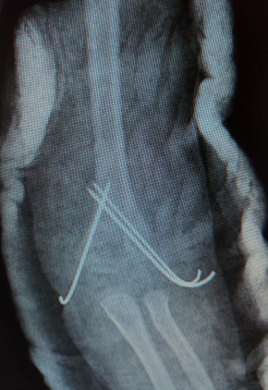

術后復查X片:提示骨折對位對線解剖復位,克氏針置入位置良好

手術后圖片:僅有3個克氏針針孔,幾乎無疤痕形成,且克氏針外置,術后6周即可拔出克氏針,無需住院開刀取出。